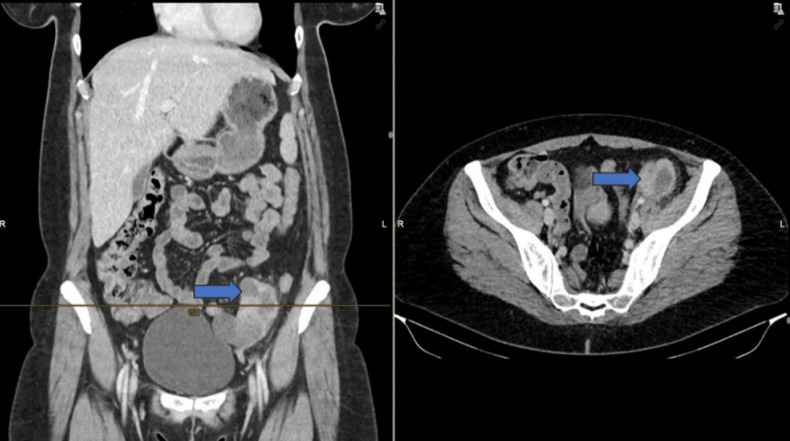

Leiomyosarcomas (LMS) arise from smooth muscle and represents only 6% of all sarcomas. LMS originating from major blood vessels, called vascular LMS, are detected mostly in the inferior vena cava. Arterial LMS are a rarity. We present a 43-year-old patient with a LMS arising from the left external iliac artery. The patient was referred to us with symptoms of left lower abdominal pain extending to the left limb and underwent a contrast computed tomography which suggested a suspicious mass near the left iliac vessels. She underwent laparoscopic excision of the tumour, whose histological examination revealed an LMS G2 arising from the external iliac artery. Immunohistochemically CD34, p53, Desmin, as well as smooth muscle actin, tested positive.

平滑肌肉瘤(LMS)起源于平滑肌,仅占所有肉瘤的6%。起源于大血管的LMS称为血管性LMS,多见于下腔静脉。动脉性LMS很少见。我们提出了一个43岁的患者LMS起源于左髂外动脉。患者以左下腹部疼痛延伸至左下肢的症状来就诊,并进行了对比计算机断层扫描,发现左侧髂血管附近有可疑肿块。她接受了腹腔镜肿瘤切除术,其组织学检查显示LMS G2起源于髂外动脉。免疫组织化学CD34、p53、Desmin以及平滑肌肌动蛋白检测呈阳性。